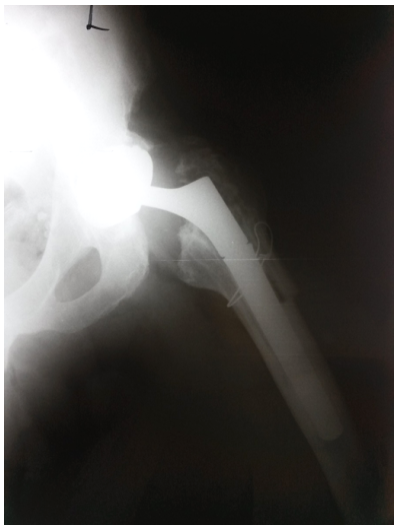

The patient is a 61-year-old, Caucasian man measuring 180cm in height and 100kg in weight, with body mass index of 30.86 (BMI). He was diagnosed with a bilateral hip osteoarthritis and admitted to our Department in November 2009 when total hip arthroplasty (Lima SPH-ST/C2, Lima International, Udine, Italy) of the right hip was performed. Subsequent total hip arthroplasty (Lima SPH-ST/C2, Lima International, Udine, Italy) of the left hip was performed in November 2010 (Figure 1). The patient underwent regular ambulatory controls with clinical and radiology examinations. Because of the aseptic loosening of femoral stem (stem subsidence) a revision surgery was made in February 2014. Revision femoral stem was implanted (Lima revision, Lima International, Udine, Italy) (Figure 2) using trans femoral approach according to Wagner in the lateral decubitus position.9 Femoral component was a cementless modular porous-coated stem made of titanium alloy with distal anchoring (tapered, fluted). Size of femoral stem was 22x140mm with the proximal part length of 70mm (total stem length 210mm). Postoperative course was without complications. Patient felt a sudden sharp pain in his left hip while walking in October 2015, 20 months after the revision procedure. Limping and the pain in left hip were increasing daily. He presented to our Department with the leg held in the external rotation and with decreased movements in hip joint. Plain radiograph showed a fracture of the revision femoral component of the left hip (Figure 3). The patient underwent a planned revision surgery procedure. Trans femoral approach according to Wagner was used again.9 Fracture was found at a junction between proximal and distal part of the stem (Figures 4 & 5). Extraction of the distal part of the stem was performed using technique developed at our Department.10 Proximal part is easy to extract without any complications. Problem is with distal part that is firmly fixed in the bone. It was removed with a special longitudinal osteotomy through the anterior cortex extending distally for 15cm. It was then followed by a transversal osteotomy 2cm below the tip of the femoral stump to allow enough space for two locking pliers. Simultaneously using a lamina spreader on the distal part, the broken stem was extracted while hammering on two locking pliers. Cementless revision femoral stem was implanted in a standard manner (Figure 6).

Figure 6 Plain radiograph postoperatively.